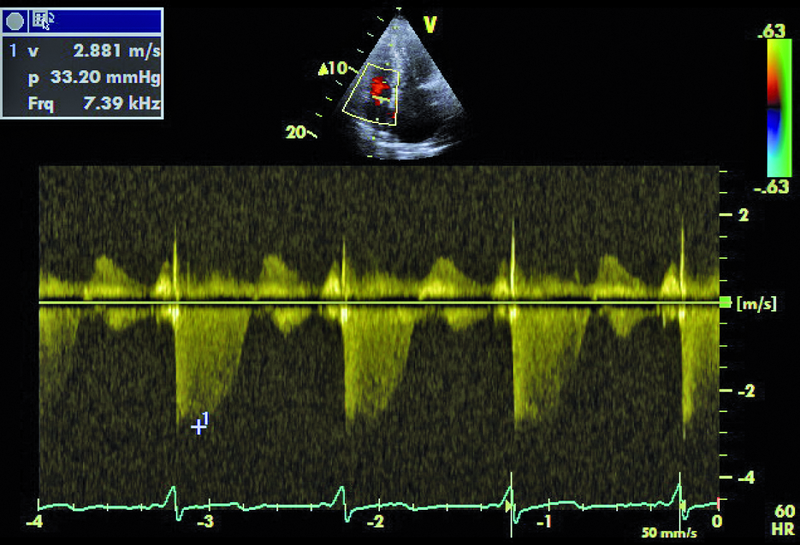

Kobieta, lat 55. Jakie patologie można rozpoznać na zamieszczonych rycinach?

3. Małe nadciśnienie płucne (ryc. 4).